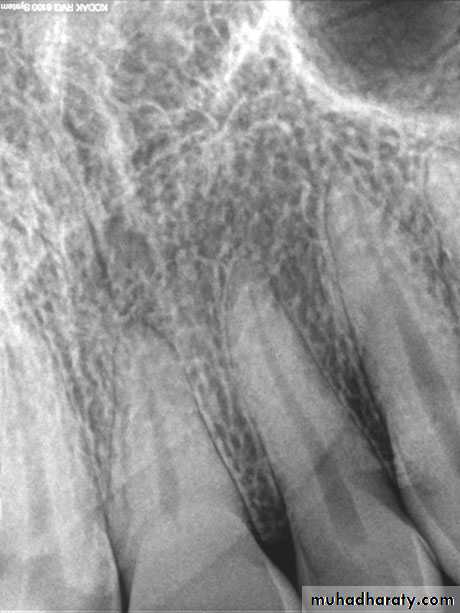

Normal Apical TissuesIn this category the patient is asymptomatic and the tooth responds normally to percussion and palpation testing. The radiograph reveals an intact lamina dura and periodontal ligament space around all the root apices.

Alveolar bone or alveolar process is that part of bone of the jaws housing the sockets for the teeth. It consists of outer cortical plate, a central spongy or cancellous bone, and bone lining the sockets. Bone matrix contains IGFs, TGF- β , BMPs, FGF, and PDGF.

Teeth with acute apical periodontitis are usually symptomatic and painful to bite and percussion which results from mechanical allodynia and hyperalgesia.Radiographic examination usually does not show periapical bone destruction of the involved tooth in acute apical periodontitis, although occasional slight widening of the apical periodontal ligament space and loss of the apical lamina dura of the involved tooth may be present.